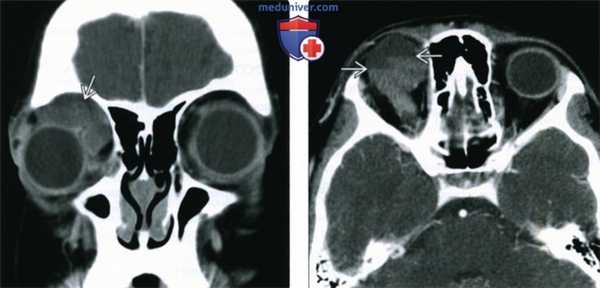

КТ в горизонтальной плоскости с контрастированием: накапливающая контраст ретробульбарная гемангиома.

(Слева) У ребенка с периодически усиливающимся экзофтальмом при КТ с КУ в корональной проекции в верхнемедиальном квадранте переднего отдела глазницы определяется дольчатое образование от средней до низкой плотности, вызывающее смещение глазного яблока.

(Справа) При КТ с КУ в аксиальной проекции у этого же пациента в толще образования определяются множественные лакуны, содержащие жидкости различной плотности с отчетливыми уровнями. Более плотные длительно существующие продукты разложения крови оседают книзу.